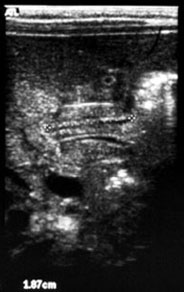

Pediatric Radiology > Abdominal > Upper GI > Hypertrophic Pyloric Stenosis - Sonographic Features

Hypertrophic Pyloric Stenosis - Sonographic Features

Hypoechoic ring of hypertrophic pyloric muscle around echogenic mucosa

centrally on cross section |